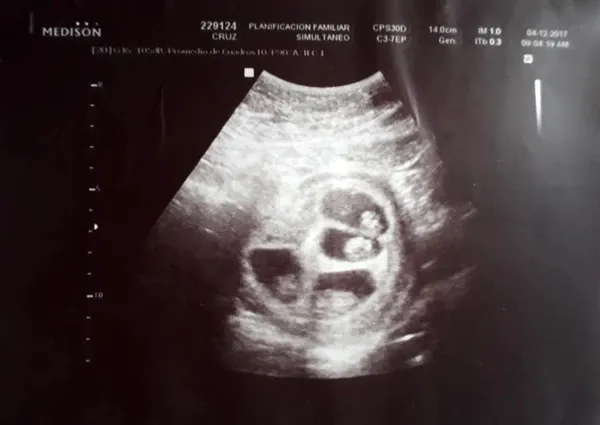

“Así que fuimos a hacer la ecografía. La ecógrafa me puso el gel en la panza y, apenas miró el monitor, se le transformó la cara. Miraba la pantalla, abría grande los ojos y repetía: ‘No puede ser’. No dijo nada y salió a buscar a más médicos”, cuenta. “Miré la pantalla y pensé que era cáncer, pensé que todo eso que se veía eran tumores y no había sabido cómo decírmelo”.

Luciano se quedó en silencio cuando su novia lo miró asustada. “Yo también pensé que le habían encontrado una enfermedad”, confiesa a Infobae. La ecógrafa volvió a entrar al consultorio acompañada de un obstetra y otra especialista en diagnóstico por imágenes. “Decían ‘no puede ser, mirá’, ‘uhh’ ‘siii, es así’, ‘nunca vi algo así’. Estaba tan asustada que no me animaba a preguntar”.

Cuando se animó a preguntar qué estaba pasando, la respuesta fue: “Bueno papis, están esperando cuatro bebés. Parece que dos son gemelos y los otros dos son mellizos”. Jéssica empezó a llorar: “Pensé ‘mi mamá me mata’. Estuvimos todo el viaje de vuelta pensando excusas, porque le habíamos dicho que íbamos al gastroenterólogo. Pero se ve que ella ya sospechaba y nos estaba esperando en la puerta”.

La siguiente ecografía mostró que cada uno estaba gestándose en una bolsa diferente. Y pese a que le dijeron que era probable que pasara el embarazo internada y que alguno de los cuatrillizos no llegara a desarrollarse, los bebés -dos varones, una nena y un dudoso- están mejor de lo que esperaban. El más grande ya pesa 1,405 kg, el que sigue 1,210 kg., el otro 1,200 kg. y la nena 957 gramos.